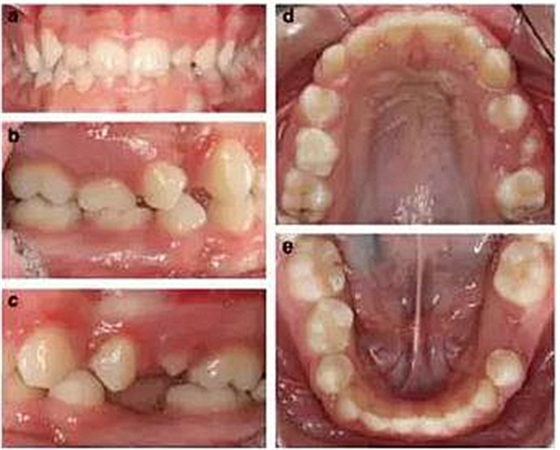

患者 女 13歲

檢查:

患者面型對(duì)稱,面上下比例對(duì)稱,輕度凸面型,鼻唇角正常;

輕度牙齦炎,口腔衛(wèi)生一般,無(wú)齲?。?/span>

右側(cè)II類磨牙關(guān)系和尖牙關(guān)系,左側(cè)I類磨牙關(guān)系和尖牙關(guān)系;

深覆合,前牙輕度不齊,下中線右偏2mm;

上下頜右側(cè)第二乳磨牙存,其余乳磨牙已脫落;